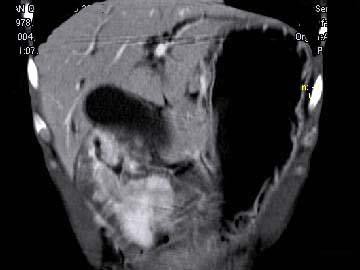

根据所提供的图像,最可能的诊断为()

• A.胃淋巴瘤

• B.胃癌

• C.胃炎性病变

• D.胃平滑肌瘤

• E.间质瘤